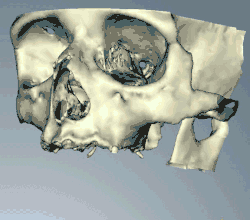

CT scans can be loaded to CAD/CAM software to create a simulation of the desired treatment. Virtual implants are then placed and a stent created on a 3D printer from the data.

When a more exacting plan is needed beyond clinical judgment, the dentist will make an acrylic guide (called a stent) prior to surgery which guides optimal positioning of the implant. Increasingly, dentists opt to get a CT scan of the jaws and any existing dentures, then plan the surgery on CAD/CAM software. The stent can then be made using stereolithography following computerized planning of a case from the CT scan. The use of CT scanning in complex cases also helps the surgeon identify and avoid vital structures such as the inferior alveolar nerve and the sinus.[49][50]:1199